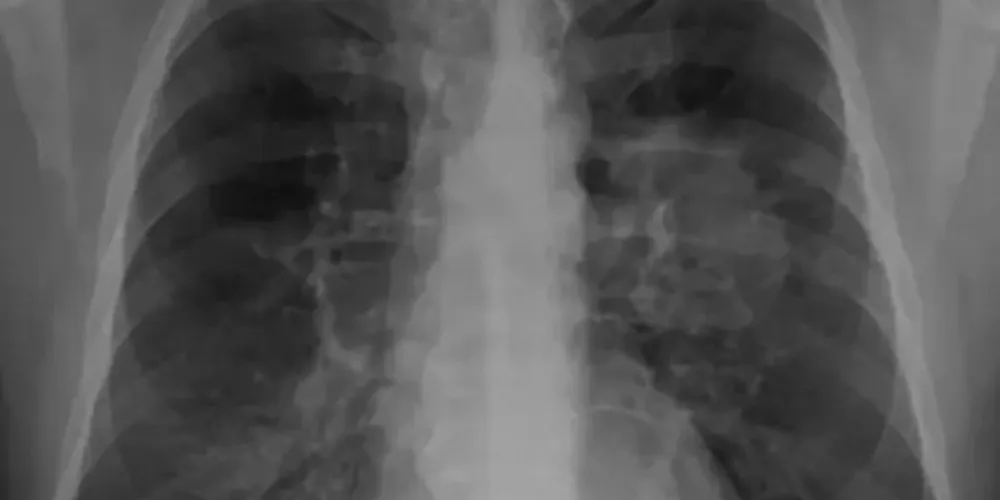

Novo remédio reduz risco de morte por câncer de pulmão em 51%

Cientistas da Universidade Yale, nos Estados Unidos, anunciaram neste domingo (4/6), que um novo medicamento teve resultados muito positivos contra câncer de pulmão, chegando a reduzir 51% o risco de morte dos pacientes que passaram por cirurgia ao longo de cinco anos. Conforme o estudo, a droga osimertinib permitiu sobrevida a 88% dos voluntários que receberam o fármaco em um ensaio clínico, contra 78% que receberam placebo.

De acordo com o anúncio, realizado no congresso da Sociedade Americana de Oncologia Clínica (ASCO), em Chicago (EUA), a droga se aplica a pacientes com um tipo específico de câncer pulmonar, relacionado a mutações no gene EGFR, que representam cerca de um quarto dos diagnósticos. Os pacientes que participaram dos testes foram operados em fases relativamente precoces do tumor (estágios 1B, 2 e 3A).